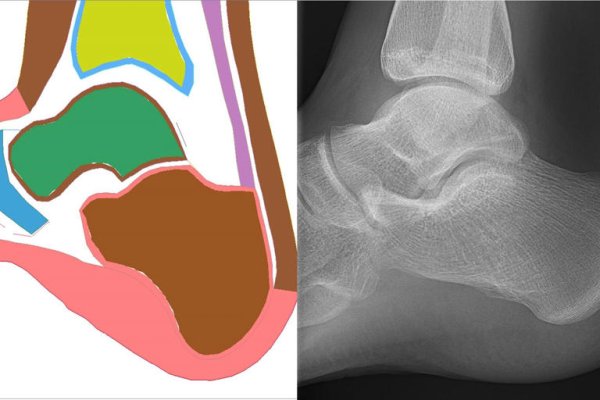

Центърът за съвместни изследвания на безопасността (CSRC) на Toyota започва четири нови проекта за биомеханични изследвания. Те изучават разликите в нараняванията между мъже и жени, както и при различни възрастови групи. Това са технологии, които могат да помогнат да предвидят кога водачът е изложен на риск от увреждане и как по-добре да превключват между автономен и „човешки“ режим на управление. За откриване на разликите в нараняванията изследователите ще използват комбинация от компютърно моделиране, експерименти с тъкани и данни от медицински образци.